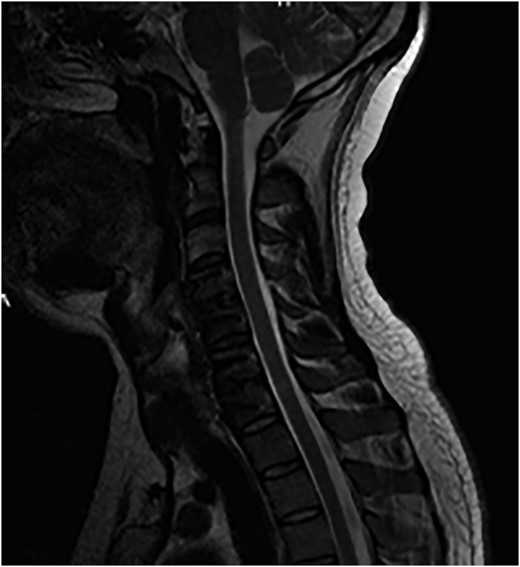

The patient underwent an awake fibre-optic intubation and was placed supine on a Mayfield frame. The subluxation of the C-Spine was reduced with 10 lbs of traction. Neurology noted to be stable after reduction. General anaesthesia induced and a standard left Smyth/Robinson approach taken to anterior cervical spine with level C4–C7 exposed and confirmed on image intensifier. Surgery was performed under full spinal cord monitoring (SCM). The operative team proceeded to perform a discectomy at C4/C5, with a noted tear in the PLL. Fragments from the canal where extracted with the aid of a microscope. Then the team moved to repeat a discectomy at C6/C7, with a small midline tear in the PLL noted. A large fragment was extracted from the canal. Subsequently satisfactory decompression of the cord was achieved and stable somatosensory evoked potentials (SSEPS) and motor evoked potentials (MEPS). Standard fusion was done using a polyethyl ethylketone (PEEK) cage filled with biphasic calcium phosphate (BCP) and a single-level anterior locking plate was employed (Figs 6 and 7).

Sagittal T2-weighted MRI images showing decompression of the cord.